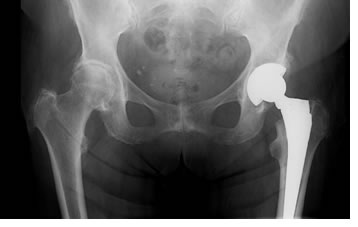

Эндопротезирование тазобедренного сустава

В отделении проводится весь спектр как первичного, так и ревизионного эндопротезирования тазобедренных суставов:

• однополюсное цементное эндопротезирование системами Austin-Moore (по показаниям);

• биполярное (DoubleCup) цементное и бесцементное (PressFit) эндопротезирование:

• первичное тотальное цементное и бесцементное эндопротезирование современными системами Link, Beznoska, Biomet, Mathys;

• ревизионное эндопротезирование.